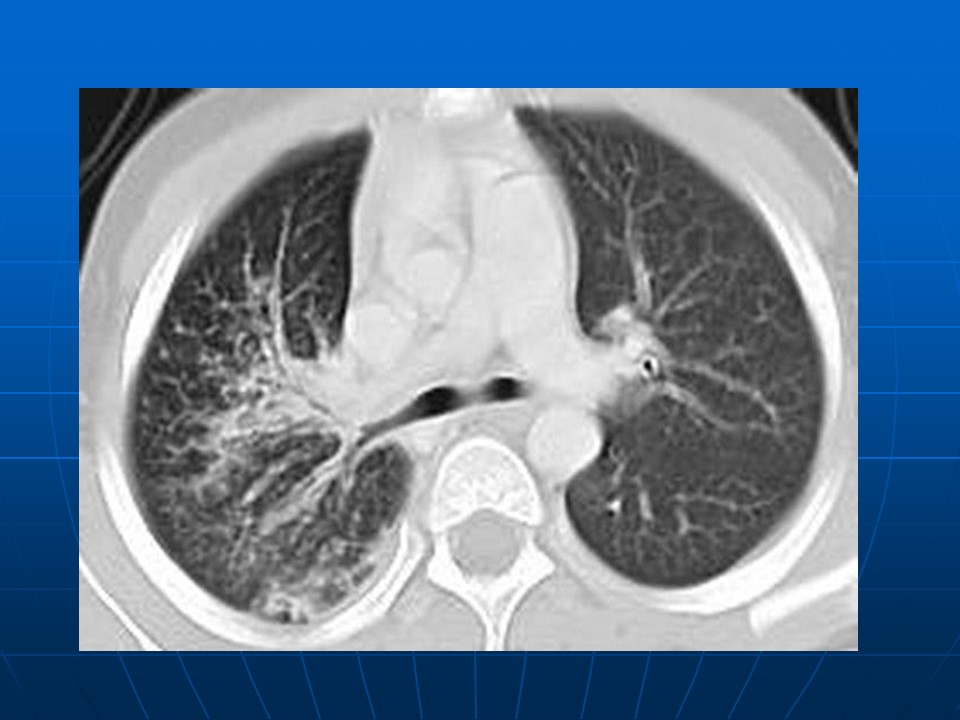

如何在影像上判断新冠病毒肺部感染是否好转